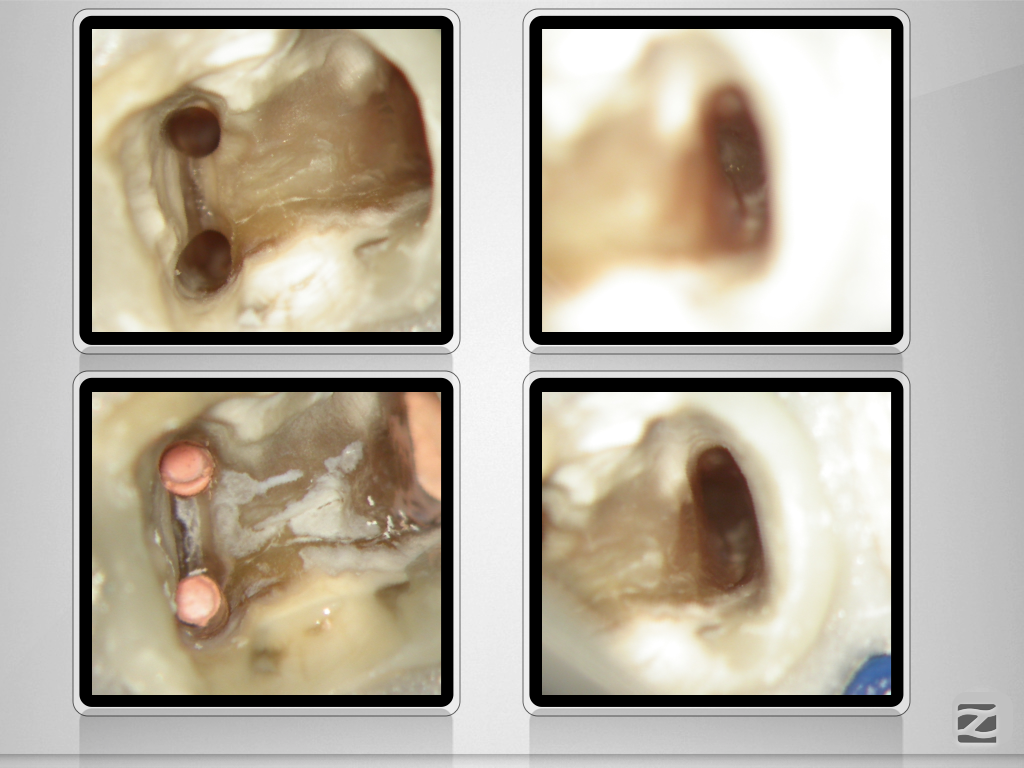

Tiefe Gabelung mit 90 Grad nach distal